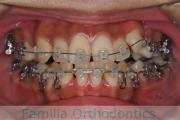

- ≫治療中 ステップ1

-

上顎

下顎

前歯の関係など

右側

正面

左側